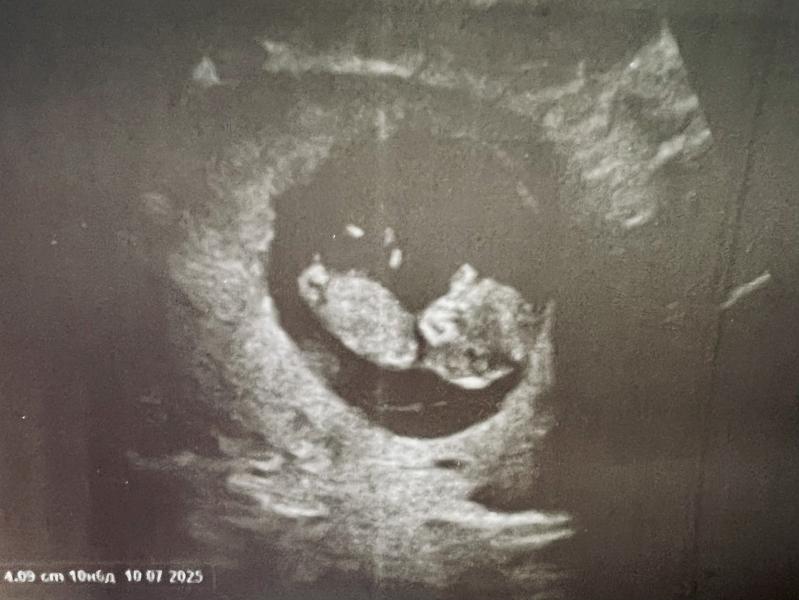

Наш предположительно мальчик 🩵

Мальчик по снимку.